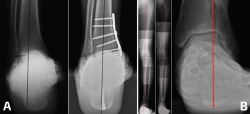

Figura 4. A: proyección de Saltzman; B: telemetría.

El estudio radiológico se realiza siempre con radiografías en carga de tobillo y pie bilateral anteroposterior, oblicua y lateral. El estudio en la actualidad se complementa con la evaluación de la alineación del retropié mediante la proyección de Saltzman (Figura 4A), además del uso de una telemetría de las extremidades inferiores, en la que idealmente se logre visualizar el calcáneo para poder determinar el verdadero punto de apoyo del eje mecánico cadera-calcáneo, que se ha propuesto como la mejor manera de planificar el manejo de la artrosis asimétrica de tobillo que involucre cirugía de realineamiento (OTT-SM/OTT de calcáneo) (Figura 4B)(14).